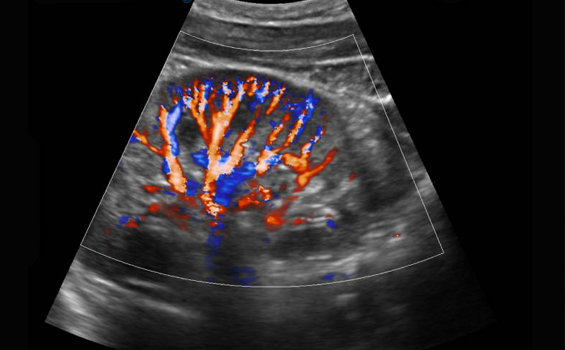

Ace Sonography Centre provides best sonography, colour Doppler and 2d Echo services with the use of best in class USG machine. We have highly qualified doctors for scanning the patient with immense first hand experience in Government as well as private setup. Diagnostic precision and excellence in patient care is our motto.

He has experience in Abdominal Ultrasound, Obstetrics and Fetal Ultrasound, and Elastography. His expertise lies in Complex USG/ CT guided procedures.